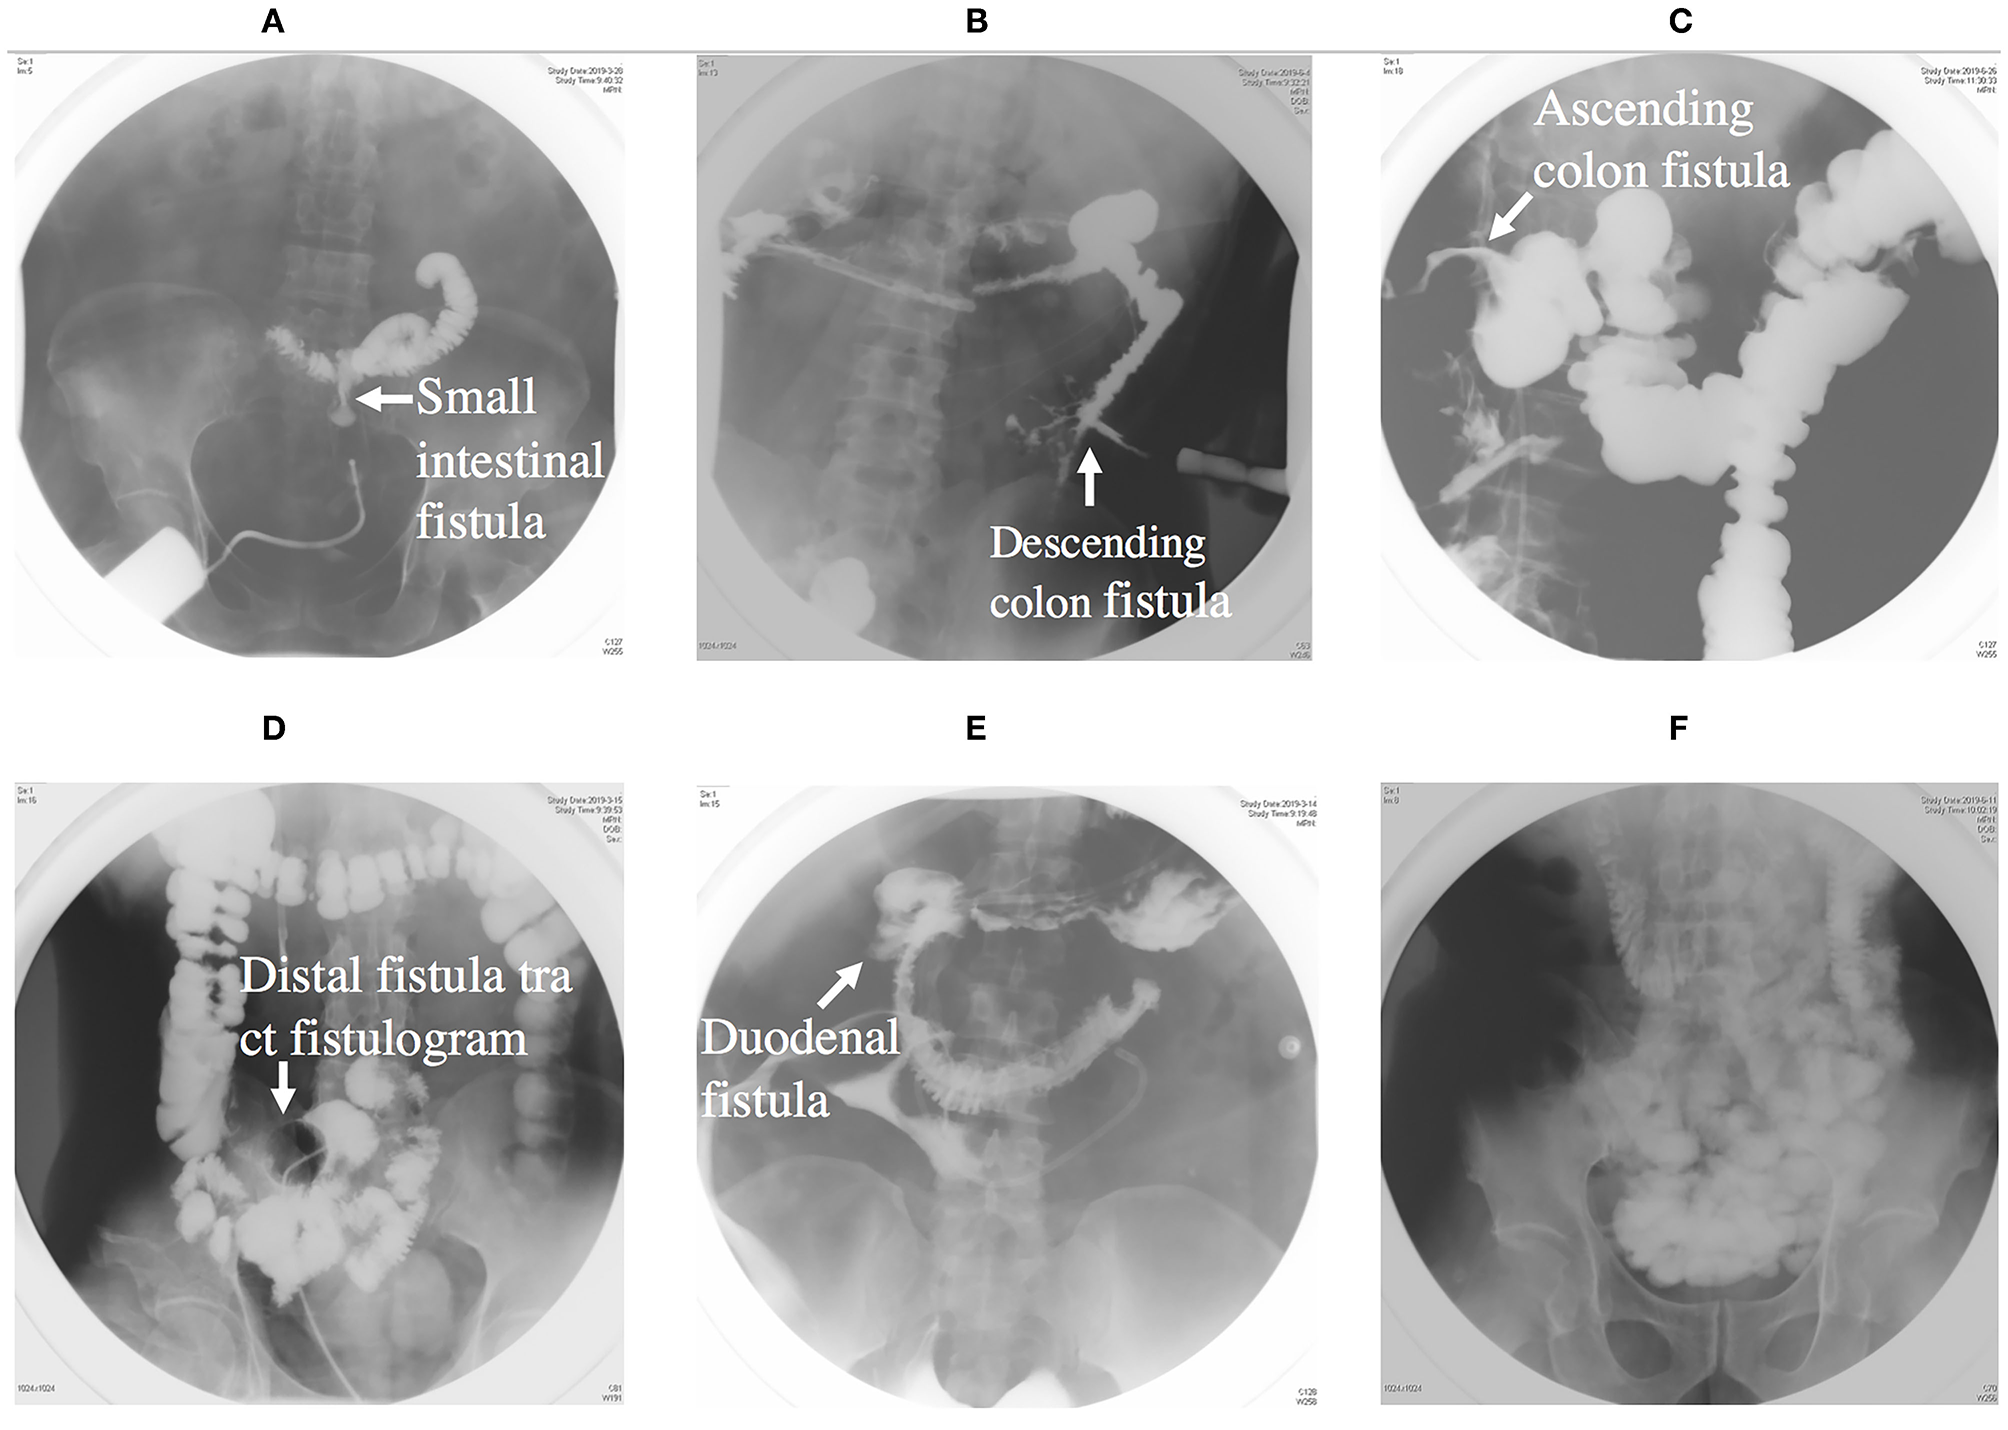

The next phase is anatomical definition and decision, during which fistulograms (Figure 3) and CT scans are performed during this period, and endoscopy is performed if necessary. Fistulograms is very important for the diagnosis of ECF. It can determine the location and length of fistula, whether it is a single fistula or multiple fistulas, and how far it is from pylorus, ileocecum, and anus. CT scan can help to determine whether there is abscess in the abdominal cavity and intestinal obstruction. Source control may be obtained with percutaneous drainage of an abscess visualized on CT scan (Figure 4). For the majority of ECF patients, fistulograms and CT are enough for diagnosis.

Figure 3. (A) Showing an intestinal fistula through fistula tract imaging. (B) Showing a descending colon fistula. (C) Showing an ascending colon fistula. (D) Showing distal intestinal tract of fistula. (E) Showing a duodenal fistula. (F) Showing proximal intestinal tract.